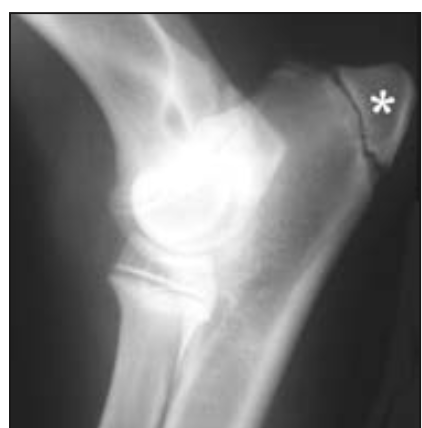

What is the term for the secondary centre of ossification (starred)?

Apophysis; additional non-articular cartilaginous protuberances that ossify and form sites of attachment for tendons and ligaments.